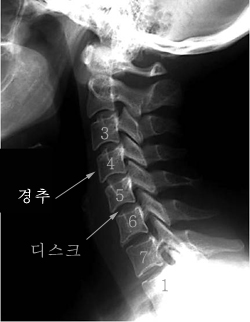

목 디스크는 목의 디스크(경추 디스크)에서 출현하는 질환으로, 경추 디스크 사이의 연골판이 터져 디스크 내부 물질이 경추 신경을 자극해 통증이나 저림증 등의 증상을 유발 해요. 목 디스크는 일상생활에서의 안 좋은 자세나 많은 운동, 부상 등이 이유가 되는 것이 될 수 있기도하고, 시간이 지날수록 발생 확률이 높아져요. 목 디스크의 증상으로는 목 부위의 통증, 팔의 저림, 근육 약화 등이 있으며, 증상이 난폭한 경우 수술 등의 치료가 필요할 수 있어요. 그리하나 대개의 경우 치료 없이도 시간이 지나면 증상이 호전되는 경우가 대부분입니다.